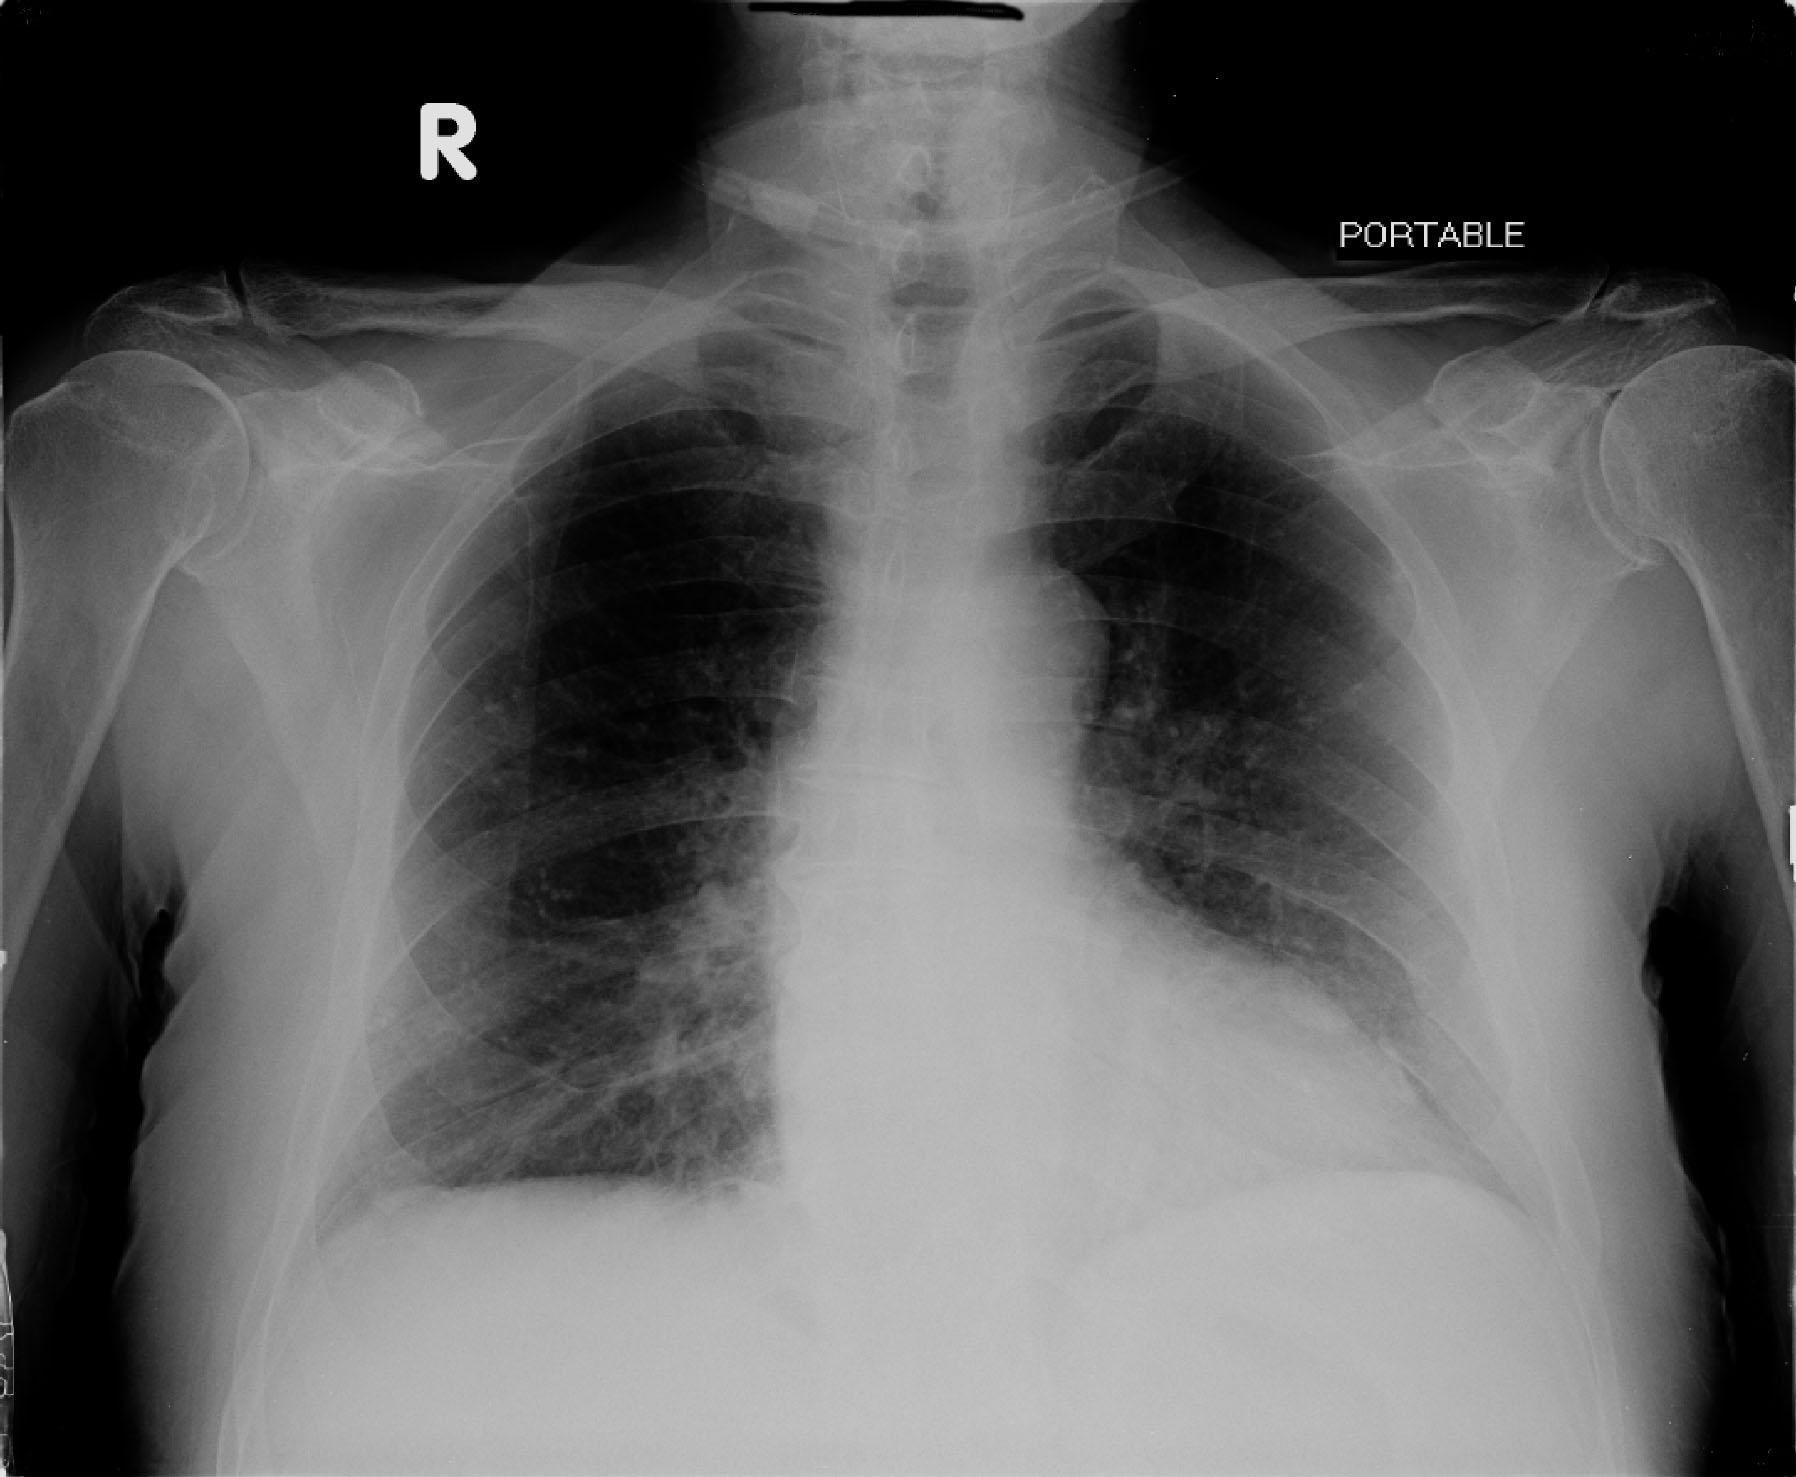

Figures